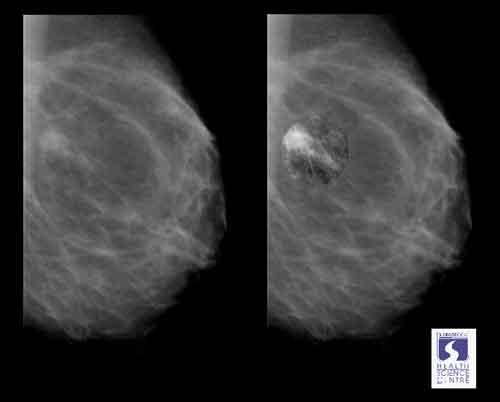

mammografia: sono più le vite salvate dai tumori killer dei rischi di sovradiagnosi

Per ogni donna che dopo una mammografia riceve trattamenti inutili contro un cancro al seno che non si svilupperà mai, due donne vengono salvate da un tumore killer. In altre parole, i benefici degli screening mammografici sono doppi rispetto ai rischi di sovradiagnosi. Una maxi revisione europea pubblicata sul ‘Journal of Medical Screening’, che ha preso in esame i dati relativi a milioni di donne, sembra mettere la parola fine al dibattito acceso da alcuni studi che contestano l’effettiva utilità di offrire screening periodici alle donne over 50, come accade in molti Paesi del mondo tra cui l’Italia.

Le principali critiche ai test mammografici ‘di massa’ portano la firma di Peter Gotzsche, direttore della Nordic Cochrane Collaboration di Copenhagen, braccio danese dell’iniziativa internazionale no profit che si propone di valutare criticamente la reale efficacia degli interventi sanitari. Dopo numerose e discusse ricerche sul tema, all’inizio di quest’anno l’esperto ha riacceso le polemiche con il libro ‘Screening mammografici: verità, bugie e controversie’. Nel volume spiega che, su 2 mila donne sottoposte a mammografia, probabilmente solo una viene salvata, mente altre 10 subiscono un danno. La nuova revisione, invece, gli dà torto e rassicura le donne: “Per ogni mille che vengono controllate ogni 2 anni, dai 50 anni di età ai 68-69 – concludono gli autori – vengono salvate da 7 a 9 vite, contro 4 casi di sovradiagnosi”. Le donne salvate, dunque, sarebbero il doppio rispetto a quelle sottoposte a trattamenti evitabili per noduli benigni.